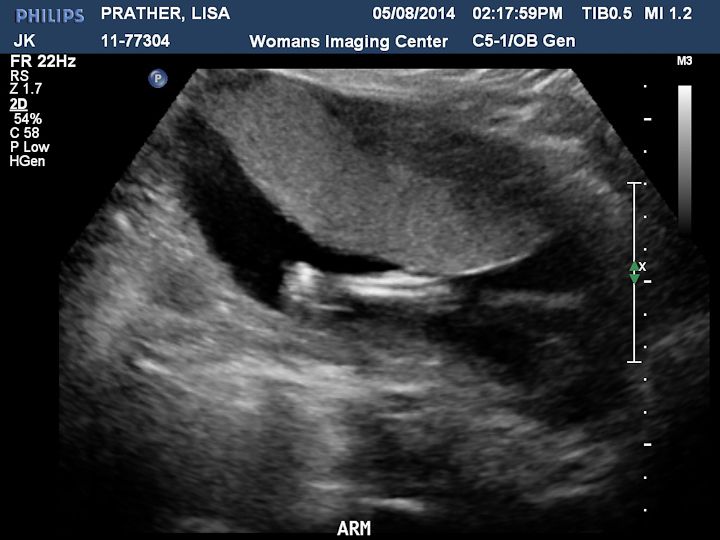

Here are some pictures we got. There is a description on each picture of what you are looking at.